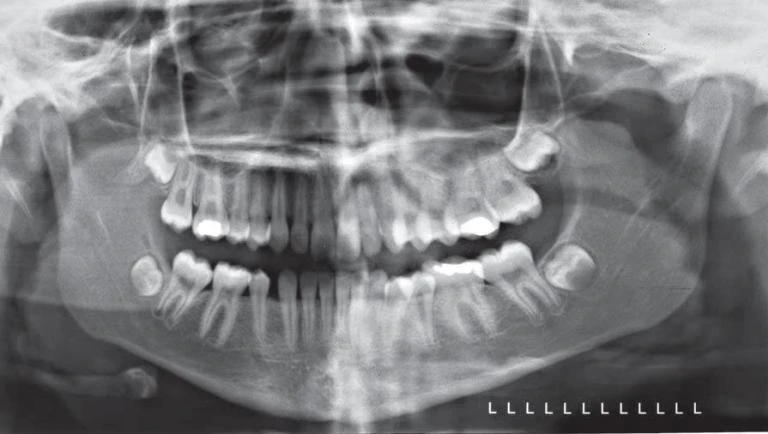

Nhà lâm sàng nên quan sát hình ảnh như thể nhìn vào bệnh nhân, với những cấu trúc bên phải của bệnh nhân sẽ nằm phía bên trái của người xem ảnh. Vì vậy hình ảnh được hiển thị cùng chiều như với hình ảnh trên phim quanh chóp và phim cánh cắn, giúp việc phân tích phim dễ dàng hơn. Điều cực kỳ quan trọng là nhận ra các mặt phẳng của bệnh nhân thể hiện trên những phần khác nhau của phim toàn cảnh. Hình ảnh trên phim toàn cảnh thật ra gồm ba hình ảnh: hình ảnh bên phải và bên trái phía sau răng nanh và một hình ảnh theo chiều trước sau từ phía trước cho đến vị trí răng nanh. Phần phía trước cũng bị biến dạng nhiều nhất và bị chồng với những cấu trúc từ đốt sống cổ. Vì vậy, phương pháp tiếp cận bằng cách hình dung phim toàn cảnh gồm hai phần hình ảnh chụp phía bên quanh một phần ảnh chụp theo chiều trước sau ở giữa, một loại hình chiếu Mercator của mặt giữa và mặt dưới. Phương pháp hình dung này cho phim toàn cảnh được mình hoạ ở hình bên dưới.